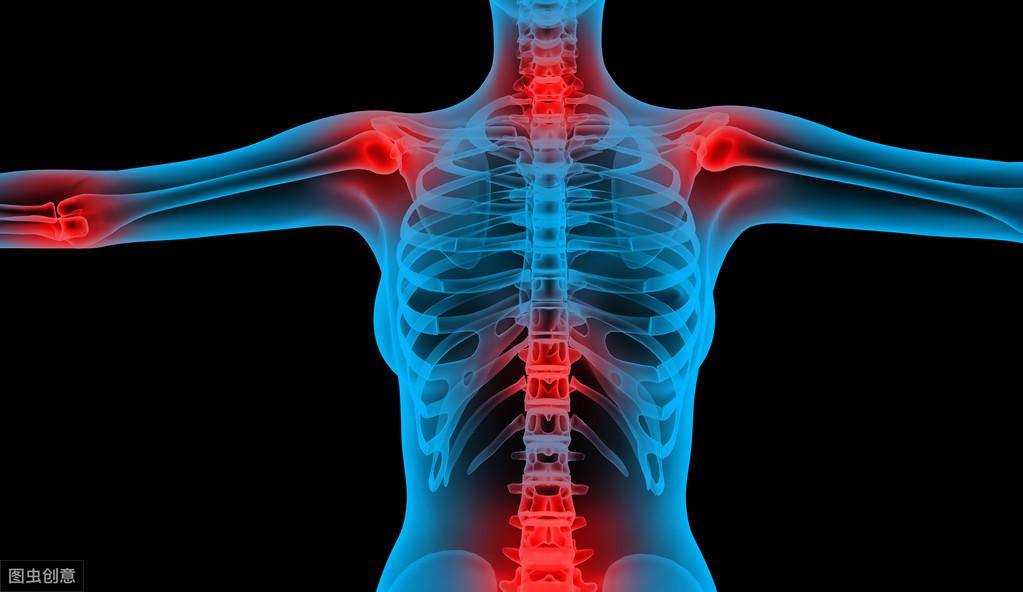

强直性脊柱炎属风湿病范畴,病因尚不明确,是以脊柱为主要病变部位的慢性病,累及骶髂关节,引起脊柱强直和纤维化,造成不同程度眼、肺、肌肉、骨骼病变,是自身免疫性疾病。

晨僵:起床时全身僵硬,身体活动后就会缓解,与一般扭伤愈活动愈疼痛不同。关节出现发炎:关节会出现肿胀、疼痛长达3个月,常见的关节有髋部、肩膀、膝盖等处。如果没有积极治疗,患者的脊椎会逐渐丧 失弹性,出现驼背、身形变矮等问题。关节周围组织发炎:当脊椎或关节持续疼痛,有时也会连带影响到周遭的韧带与肌腱引起发炎,造成疼痛。